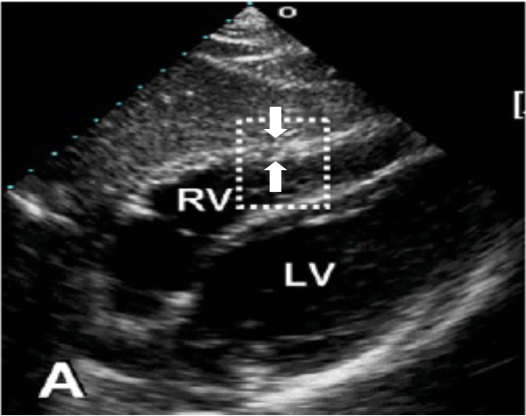

(3)右心评估:快速判断右心形态大小;室间隔有无受压和/或矛盾运动;右心收缩运动有无异常;上述异常是急性抑或慢性。